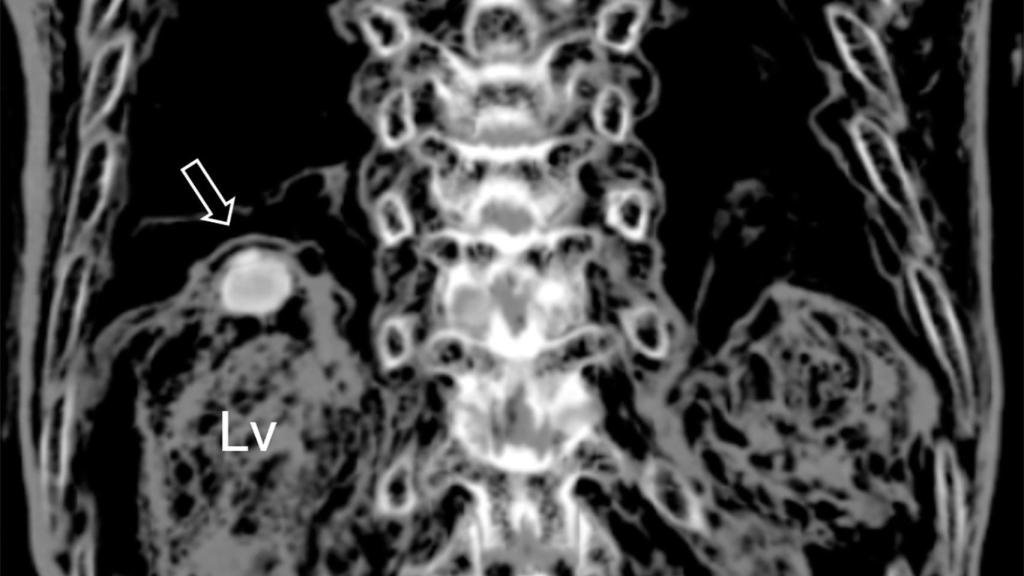

La infección detectada en el hígado de la momia.

La infección detectada en el hígado de la momia. Journal of Parasitology

Tras analizar dicha tumoración, los investigadores encontraron huevos de color marrón-dorado, de aproximadamente 85 micrómetros de largo, los cuales se habrían producido por una infección por Paragonimus westermani. En otras palabras, esto significaría que Jing Lee sufrió paragonimiasis hepática cuando murió, convirtiéndose en el caso más antiguo conocido de esta dolencia.